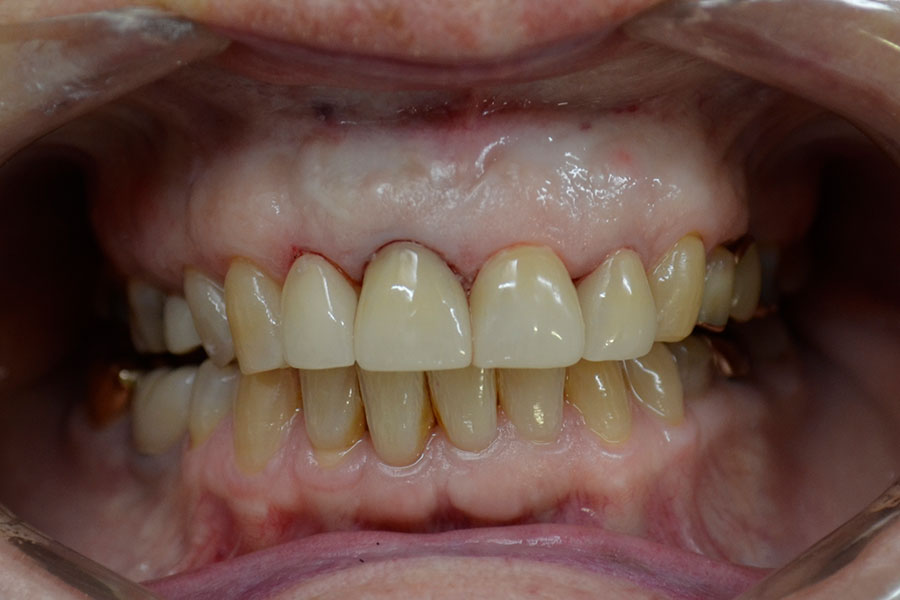

Christine had a crown on a root canal treated upper right central incisor that had a receding gum line.

Some of the white fillings on other front teeth were also stained. Pauline decided to have the crown replaced and ceramic veneers placed on other three adjacent teeth. The new crown is all ceramic and blends in more naturally with the veneers.